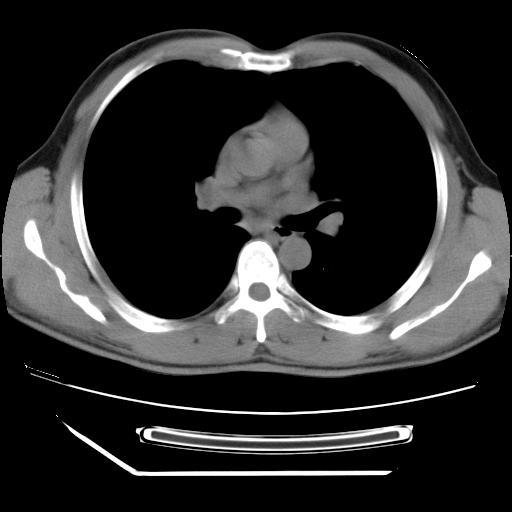

男,38岁,于2009年8月9日晚突发左侧胸痛,今x线提示左下肺阴影,为了明显确诊断,行ct检查,

血常规:嗜酸性细胞增高,单核细胞增高。

病灶发生在下叶,密度均匀,边缘模糊、毛糙,周围血管纹理增强扭曲改变,靠近胸膜处病灶胸膜反应明显。

支持考虑---球形肺炎。

左肺舌叶病变。主体病灶呈类圆形中心密度低,成液化趋势周边班片影分布

考虑肺脓肿

虽然实验室检查支持炎性病变,且病变内有坏死改变(中央呈大片状低密度影),但仍不能掉以轻心,鳞癌也可以有这种影像改变。